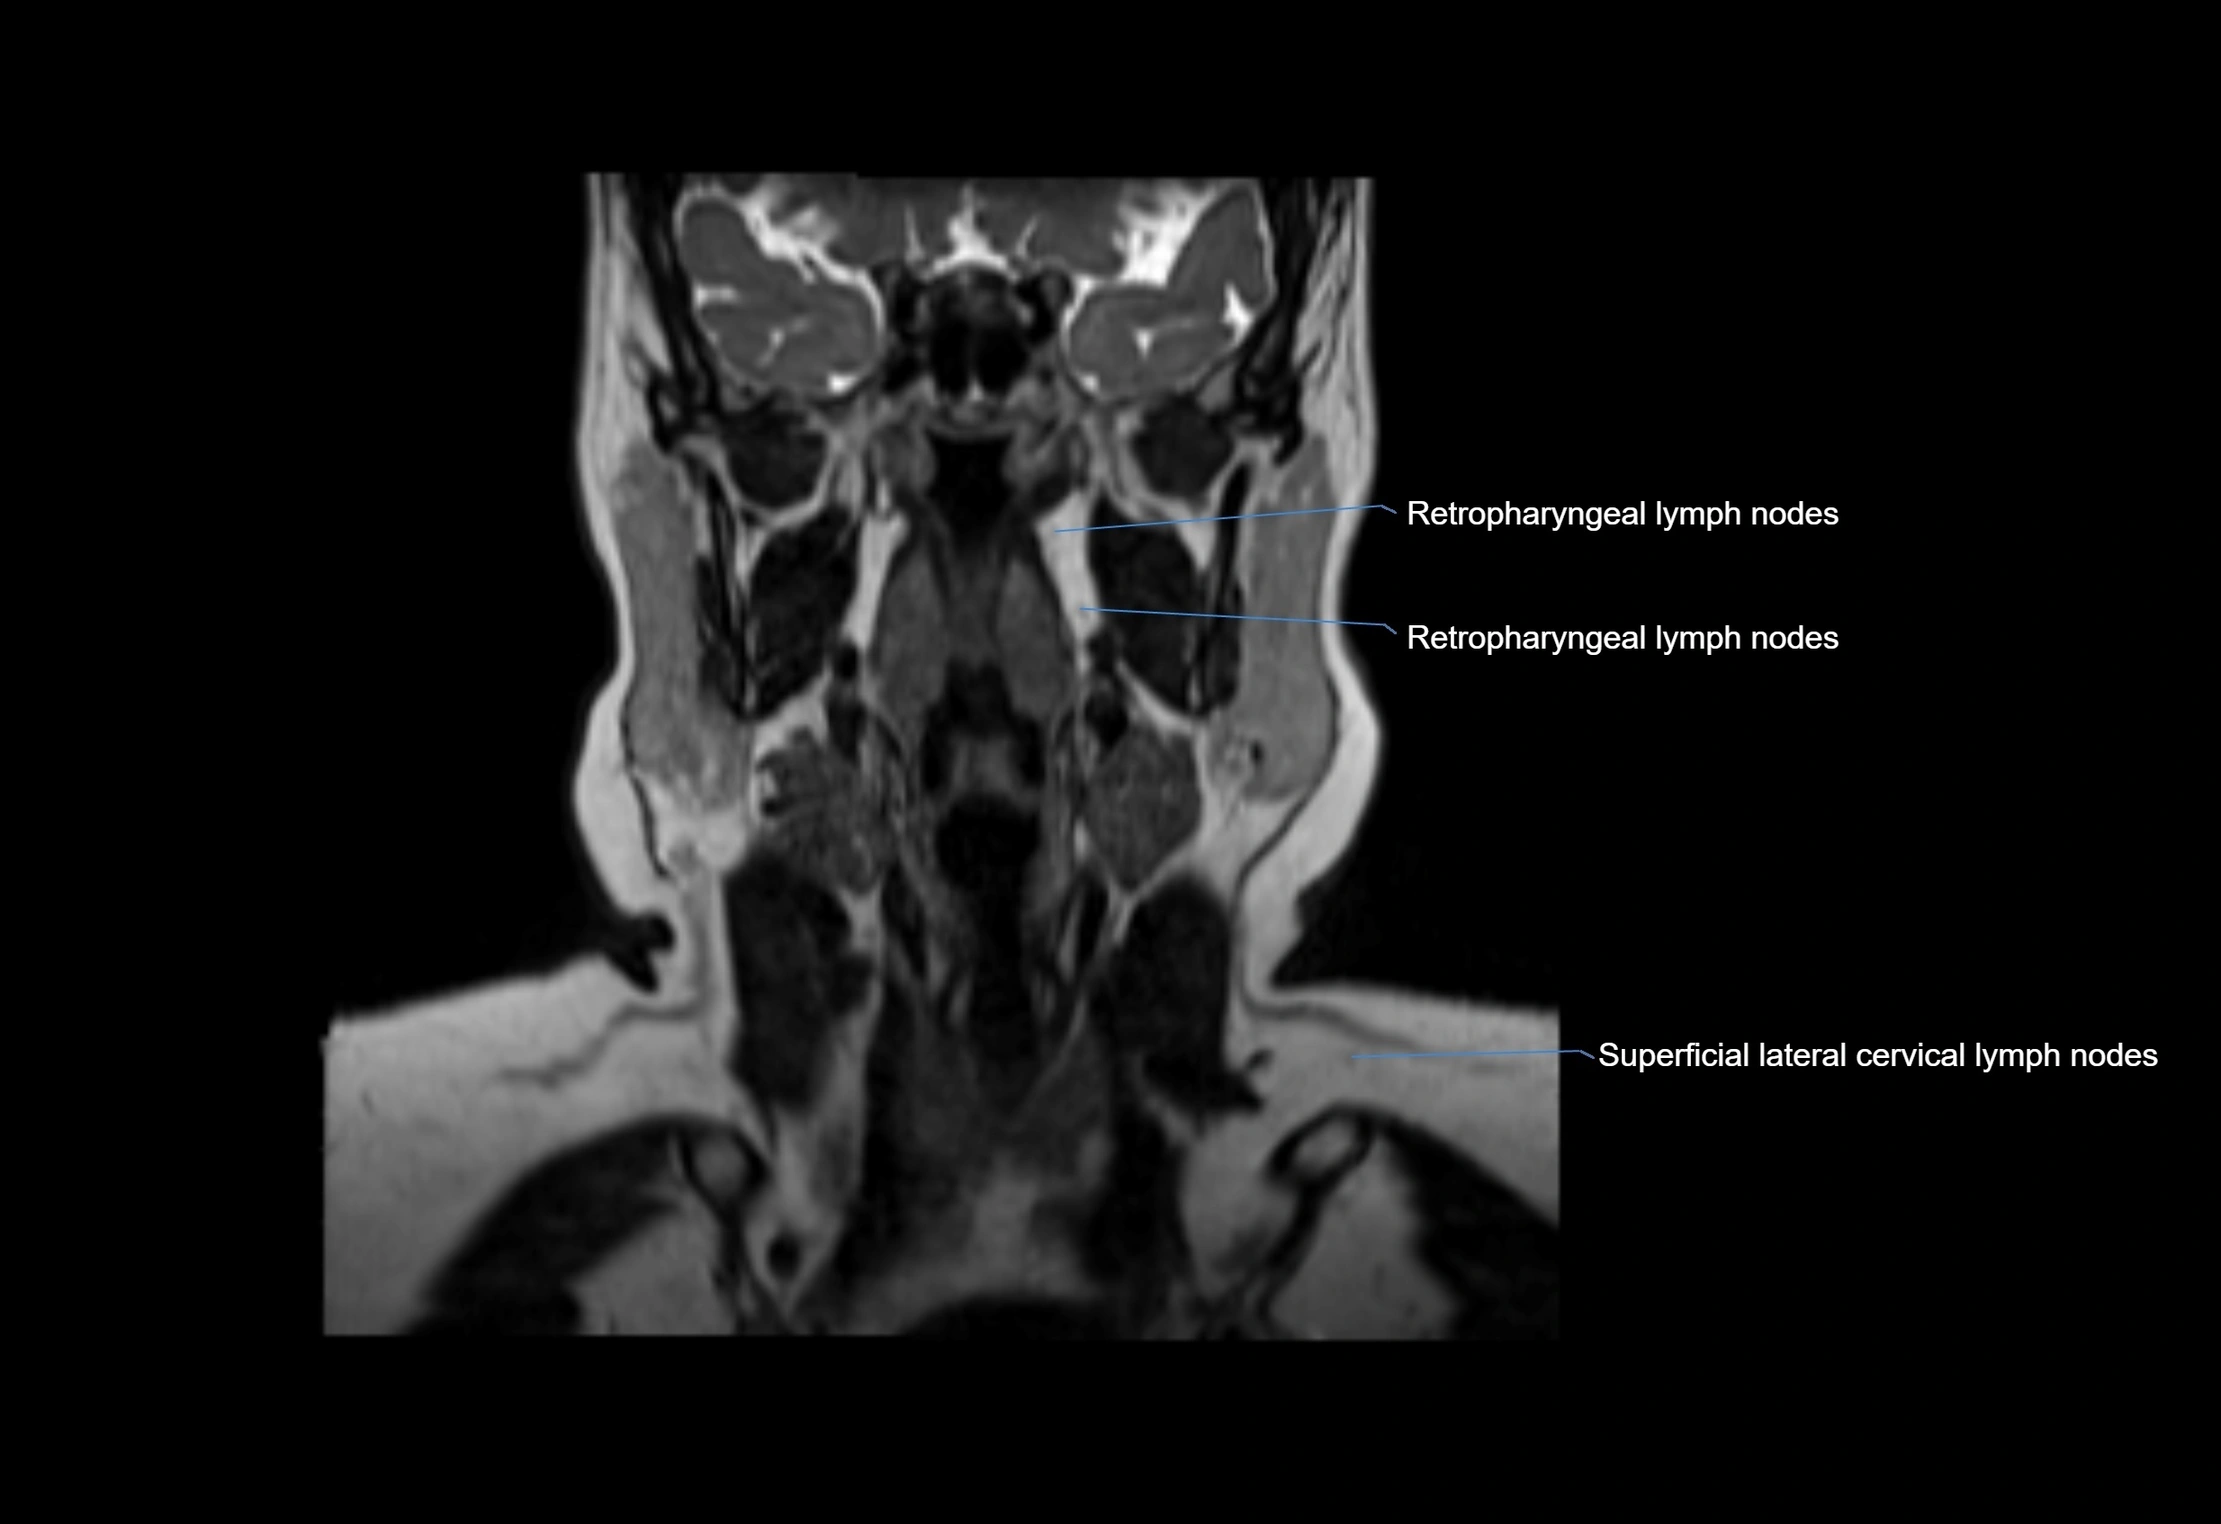

Location

• Found along primary lymph node chains, including preauricular, submandibular, parotid, and occipital regions

• Embedded in subcutaneous fat or superficial fascia, often lateral or posterior to primary nodes

• Variable in number; may occur unilaterally or bilaterally, depending on individual anatomy

MRI Appearance

T1 Post-Contrast (Gadolinium-enhanced):

• Normal nodes may show mild, homogeneous enhancement

• Inflamed or metastatic nodes demonstrate marked homogeneous or heterogeneous enhancement, highlighting the cortex and fatty hilum

• Post-contrast imaging helps detect early metastasis, infection, or inflammatory changes

MRI images

image